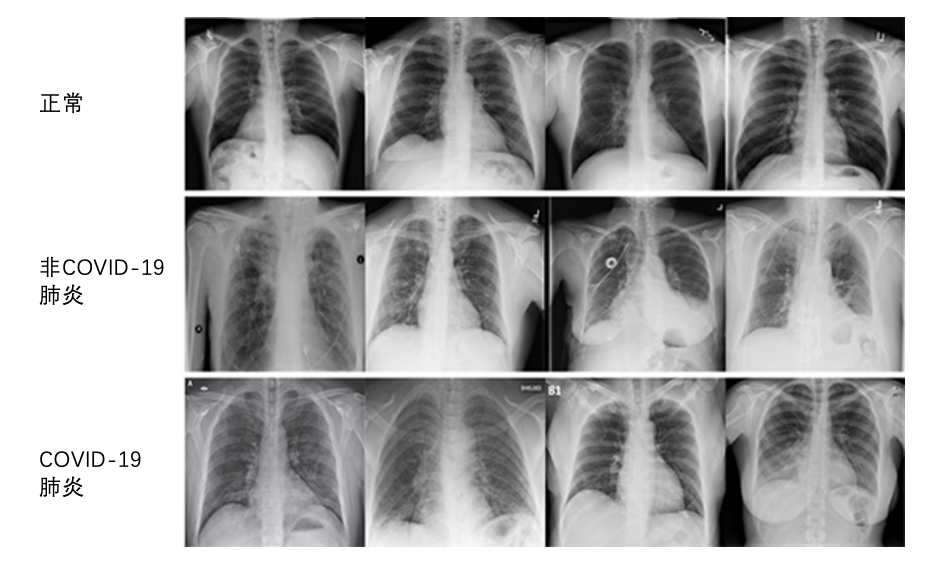

一项称为F分数的测量对于深度学习系统的整体准确性进行了评估,该系统尝试准确地预测数字图像上的图案和异常。康耐视的研究人员分析了COVID-Net数据集中的近14,000张X光片图像。这些图像被分为以下三种类型:正常、非COVID-19肺炎和COVID-19肺炎。